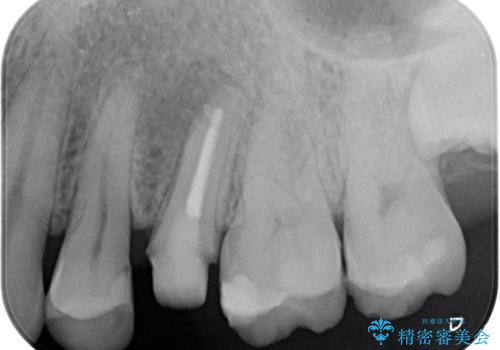

- 左上の歯茎にできものができたとのことで来院された患者様です。

術前検査より根管内の感染が疑われたため、再根管治療を行います。

根管内の感染源を可能な限り除去し洗浄しました。